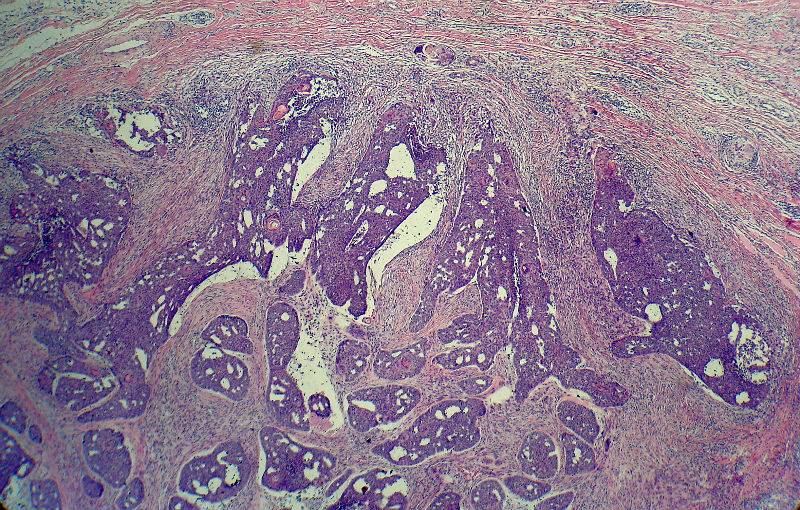

男,49岁,后枕部肿物3年,偶有破溃出血。

大体:皮肤半球形隆起,大小约2.3×2厘米,高出皮表0.8厘米,切面灰白,质地细腻。